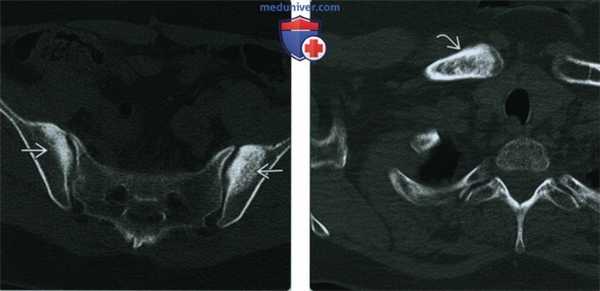

(Слева) КТ, аксиальный срез: у этого игрока регби 21 года определяется склероз, неровность и эрозии вдоль ЛС, что указывает на хронический ОЛК. КТ позволяет выявить хронические признаки ОЛК, но обычно не используется для постановки диагноза. Обратите внимание на пролиферативные изменения кости при хронических разрывах приводящих мышц.

(Справа) КТ, 3D реконструкция поверхности: у этого же пациента подтверждена неровность ЛС, что указывает на длительный ОЛК. (Слева) При рентгенографии в передне-задней проекции у регбиста 20 лет определяется асимметричный склероз кости и эрозии при хроническом ОЛК. Значительный склероз и эрозии свидетельствуют о длительном течении. Признаки острого ОЛК в первую очередь включают в себя отек костного мозга, который не визуализируется при рентгенографии.

(Слева) При рентгенографии в передне-задней проекции у игрока в американский футбол с постоянной двусторонней болью в паху определяется небольшой субхондральный склероз и ранняя резорбция в области ЛСВ, которые иногда могут остаться незамеченными.

(Справа) Сцинтиграфия костей с МДФ, меченной Тс-99, в передне-задней проекции: у этот же пациента определяется интенсивное поглощение радиометки вокруг ЛС при картине, схожей с субхондральным отеком костного мозга, который визуализируется на МРТ при остром ОЛК. ОЛК часто не визуализируется или слабо выражен при рентгенографии. (Слева) МРТ Т2ВИ, режим подавления сигнала от жира, косой аксиальный срез: у женщины 32 лет с левосторонней болью в паху и правосторонней болью в тазобедренном суставе определяются асимметричный субхондральный отек костного мозга слева и гипертрофия капсулы ЛС с ранними пролиферативными изменениями, свидетельствующие о ОЛК вследствие дестабилизирующей травмы.